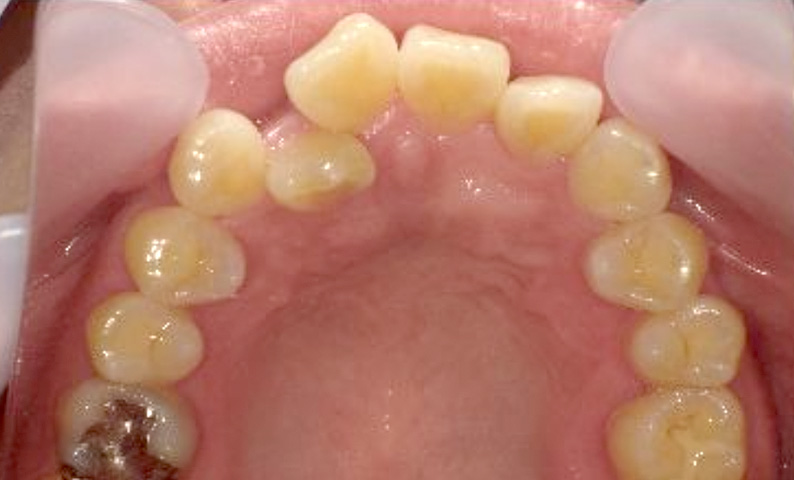

症例_003 下顎だけの部分矯正

治療期間:10ヶ月金額:24万円+税女性前歯のガタガタ下の前歯だけ上顎は補綴治療中

| Before | After |